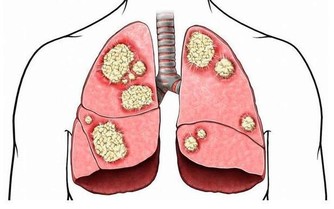

痛風到底是咋回事

痛風原因

人體內嘌呤來源有體內細胞分解而來,和從食物中獲取而來這兩種情況。如果人體產生嘌呤,會代謝為嘌呤,一旦尿酸代謝出現障礙就會引起痛風。如果患者平時有喝酒、吃肉等習慣,且身材比較肥胖,很容易得痛風。